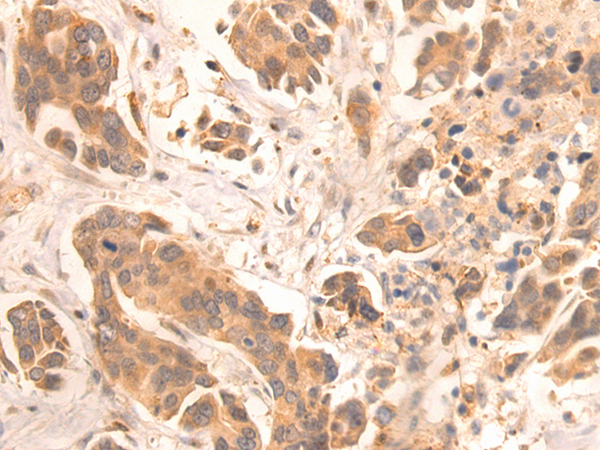

IHC positive control: |

Human gastric cancer |

IHC Recommend dilution: |

25-100 |